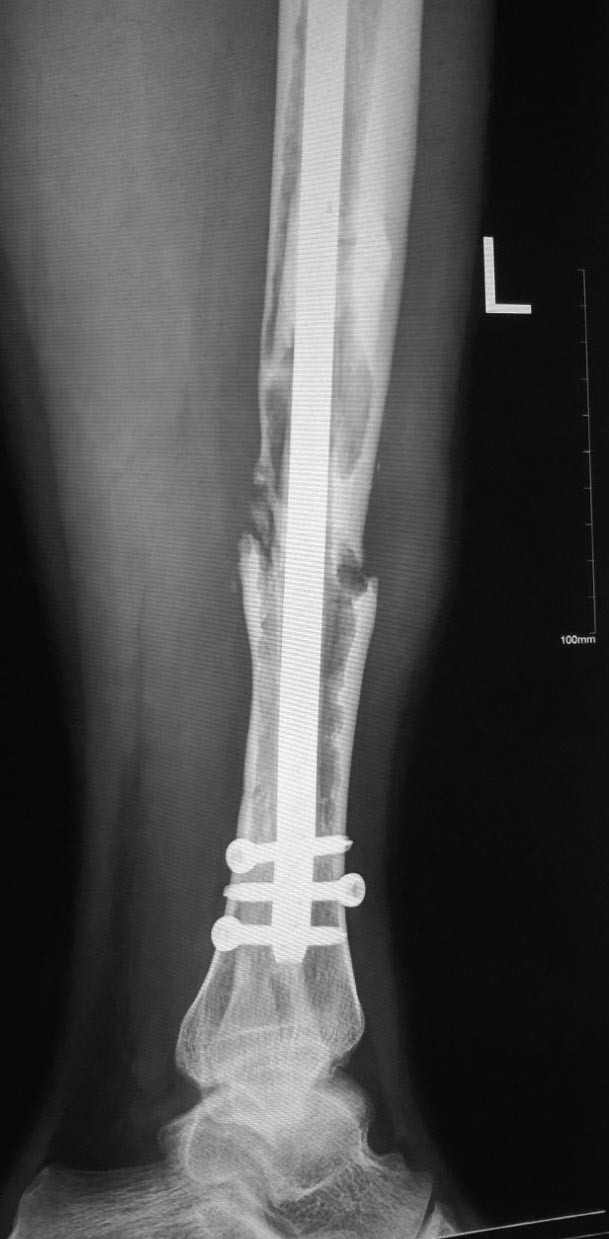

[Ortho] Несращение большеберцовой кости

Виталий Валерьевич, добрый день. Пациент сейчас в другом городе, прислал

снимки без проксимального отдела. Боковую проекцию добавлю.